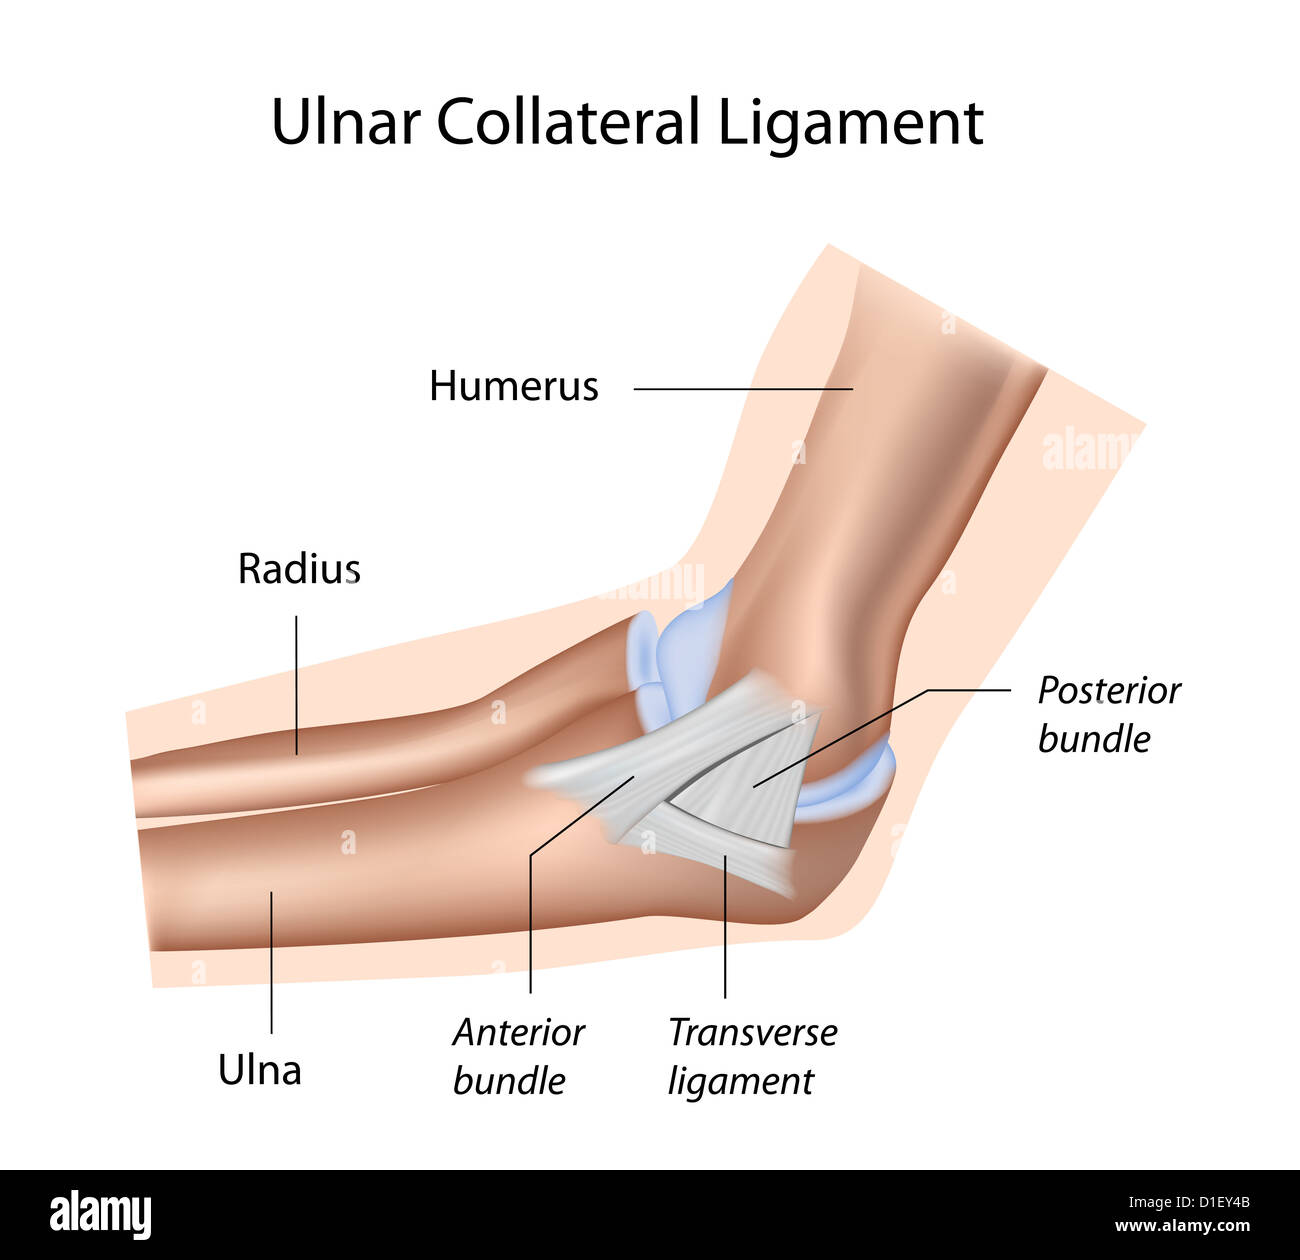

Ulnar collateral ligament of elbow Stock Photohttps://www.alamy.com/image-license-details/?v=1https://www.alamy.com/stock-photo-ulnar-collateral-ligament-of-elbow-52574379.html

Ulnar collateral ligament of elbow Stock Photohttps://www.alamy.com/image-license-details/?v=1https://www.alamy.com/stock-photo-ulnar-collateral-ligament-of-elbow-52574379.htmlRFD1EY4B–Ulnar collateral ligament of elbow